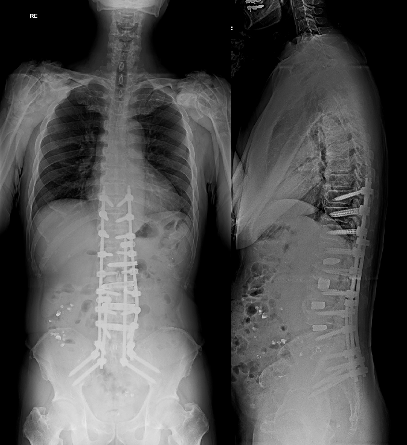

成人脊柱変形に対する矯正固定術

小児期側弯症の遺残、加齢に伴う椎間板変性による変性側弯症、椎体骨折後の変形などに対して、保存療法から手術療法まで対応しています。高齢患者さんには、二段階手術や身体への負担が少ない低侵襲固定手術、骨粗鬆症治療を組み合わせることで、合併症低減と効果的な矯正の両立を目指しています。